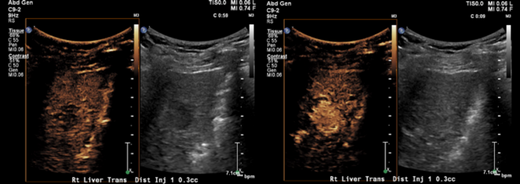

Abdominal Images

• A high-volume clinical workload offers immense learning opportunities, with more than 21,000 CT (including CT colonography, CT enterography, and CT angiography), more than 5,000 MR (including newly developed 3T pulse sequence advanced MR imaging), more than 25,000 ultrasound (including advanced vascular ultrasound and elastography), and more than 600 image-guided procedures (over the past year: liver biopsy/drainage 173, thyroid FNA 223, lymph node biopsy 159, renal biopsy 43, paracentesis 59, abdominal abscess drainage in excess of 200) in this section per year

• Rotations include 12 weeks of Body CT, 12 weeks of Body MR, eight weeks of Body Procedures, eight weeks of ultrasound, four weeks of GI/GU/Fluoroscopy, four weeks of PET, and four weeks of an elective